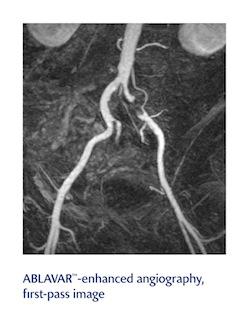

Definity, an ultrasound contrast agent for use in patients with suboptimal echocardiograms to opacify the left ventricular chamber and to improve the delineation of the left ventricular endocardial border cardiograms, and Ablavar, an MRA contrast agent indicated to evaluate aortoiliac occlusive disease (AIOD) in adults with known or suspected peripheral vascular disease (PVD), will both be offered to more than 2,500 hospitals nationwide and 76,000-plus healthcare sites. The contracts were awarded after a competitive bidding process that examined multiple factors, including pricing and clinical experience with Definity and Ablavar, as well as Lantheus’ support of the products.